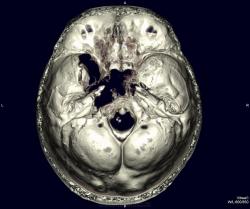

Краниофарингеома? Есть ли данные контрастирования?

Нет, контрастирования не делали. Бабушку отпустили домой, сказали, что опухоль неоперабельная. Вряд ли это краниофарингиома. Скорее это опухоль из основной пазухи или из решеток. У нас она прошла как опухоль основания черепа. Увы!

Иногда надо вовремя остановиться. Можно было бы взять биопсию. Но для пациентки это вряд ли что-либо дало, а ей уже за 80. Решили не мучить бабушку.